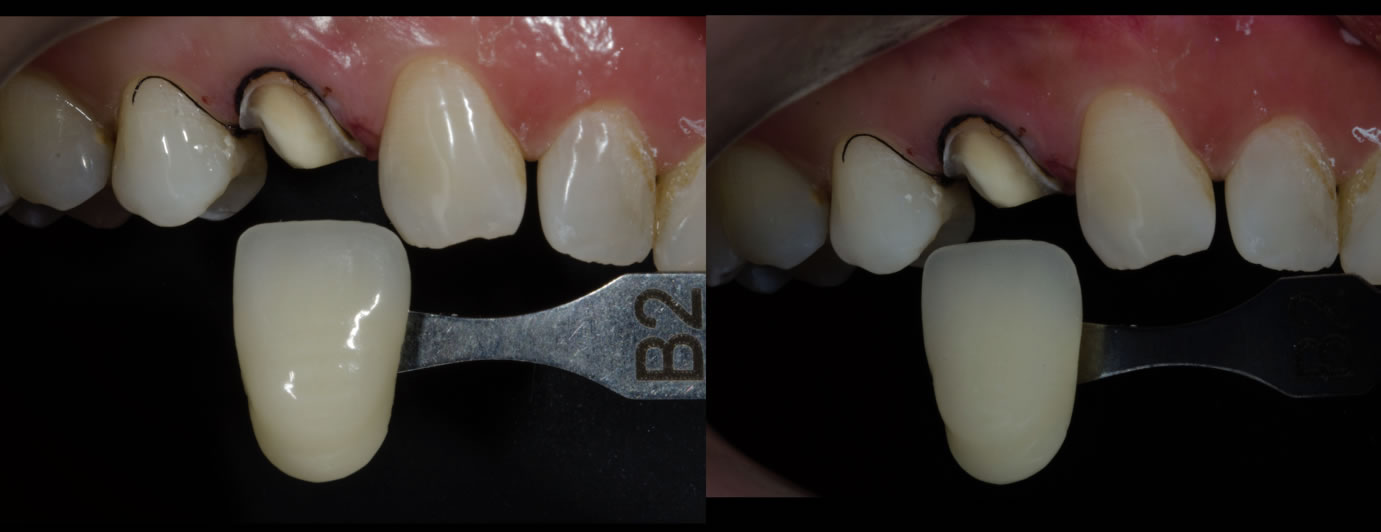

Les recommandations actuelles sont d’utiliser une barrette de référence du teintier au minimum pour donner au prothésiste un élément de comparaison.

1- Mesure au teintier électronique Easyshade ;

2- Contrôle manuel au teintier shadeguide/ 3Dmaster ;

3- Photo avec échantillon de teinte (lumière naturelle et polarisée) ;

Cas clinique N°1 : overlay Emax sur 14

Cas clinique N°1 : Couronne Emax stratifiée sur 26